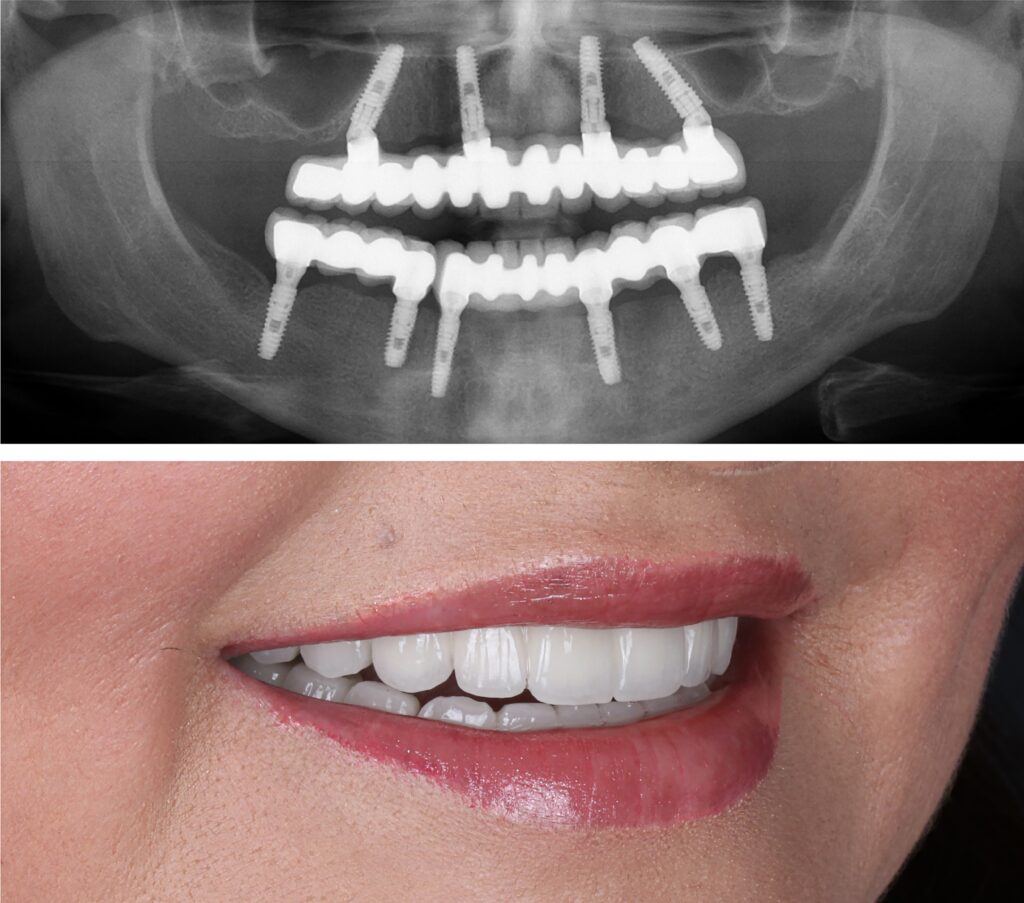

Example transformations achievable with dental implants

Every single dental implant consists of three parts – the implant, the abutment, & the crown. The implant is made of medical grade titanium. This part is surgically placed into the patient’s jaw bone and left to heal for 4-6 months afterwards.

This implant piece acts as the foundation for the rest of the tooth. Once the bone around the site has healed, the abutment and crown are placed on top of the implant. The end result is a beautiful, natural-looking new tooth!

Few people will ever be able to tell the difference between your implants and your real teeth.